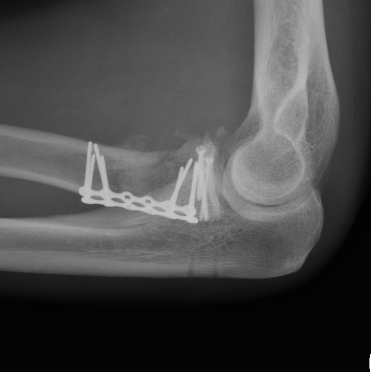

ORIF with plates

Technique

Lateral approach

- identify safe zone (90 degrees between radial styloid) and Lister's tubercle)

- lag articular surface first if required

- pre-contoured low profile plates

- distal limit is bicipital tuberosity

- check ROM intra-operatively

- plates often bulky and may limit ROM

- close annular ligament